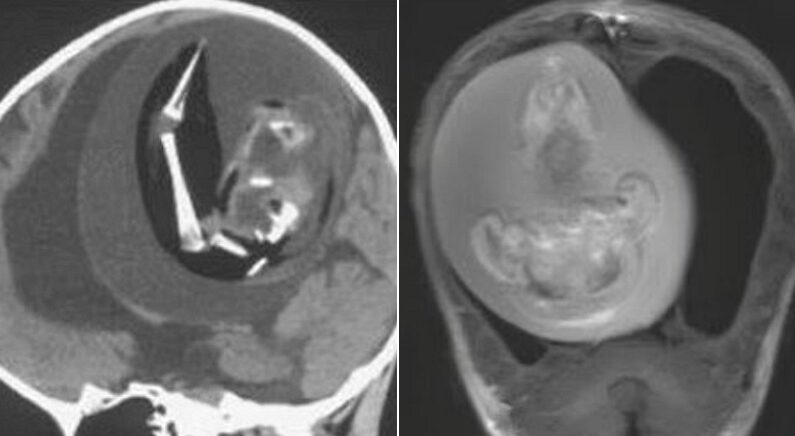

병원 의료진은 단순 종양으로 판단하고 CT 촬영을 진행했는데, 두개골 안에서 뇌를 짓누르고 있는 ‘쌍둥이 태아’가 발견된 것이다.

심지어 일란성 쌍둥이 기생 태아는 뼈와 팔, 손톱까지 자란 상태였다.